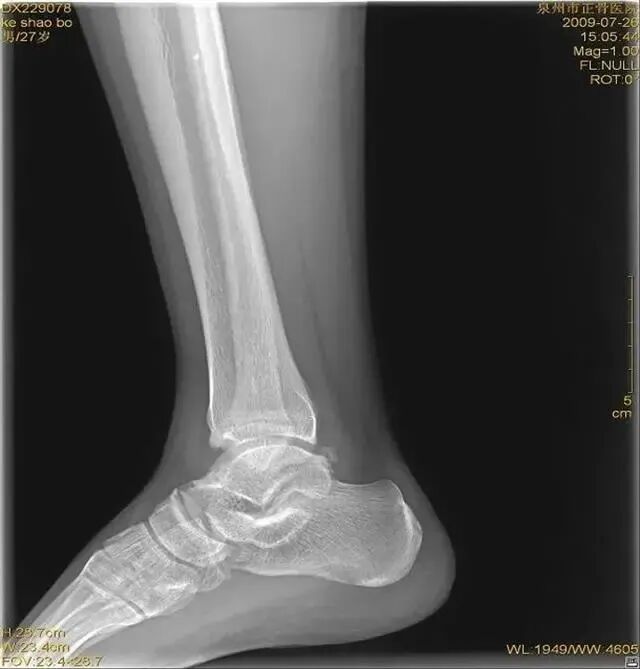

距骨体前宽后窄,当踝关节背屈时,其宽部进入踝穴,能防止踝关节向后脱位;当跖屈时,其窄部进入踝穴,则关节不稳,易向侧方活动。